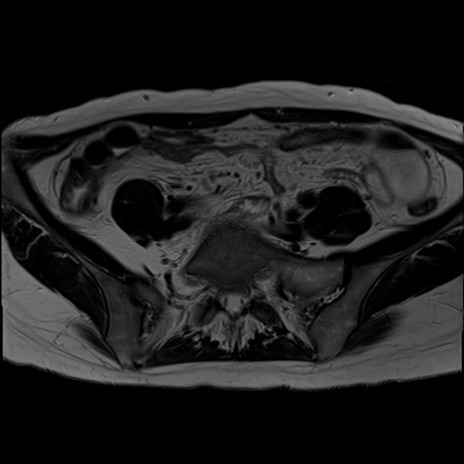

症例39 T2WI(横断像)

MRI(4日後)